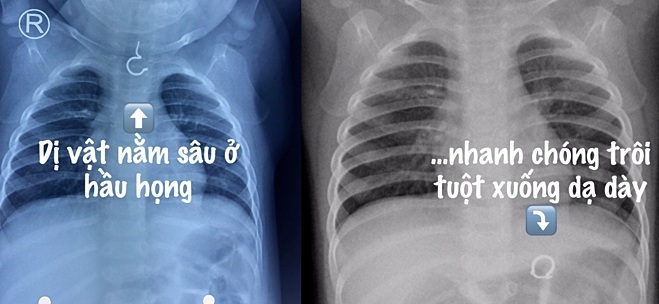

Sau khi tiếp nhận, bác sĩ khám và cho chụp X-quang phát hiện dị vật hình chiếc khuyên tai ở trong hầu họng, sau đó nhanh chóng trôi tuột xuống dạ dày.

Ảnh chụp X-quang chiếc khuyên tai lọt vào dạ dày bé gái. Ảnh:BSCC